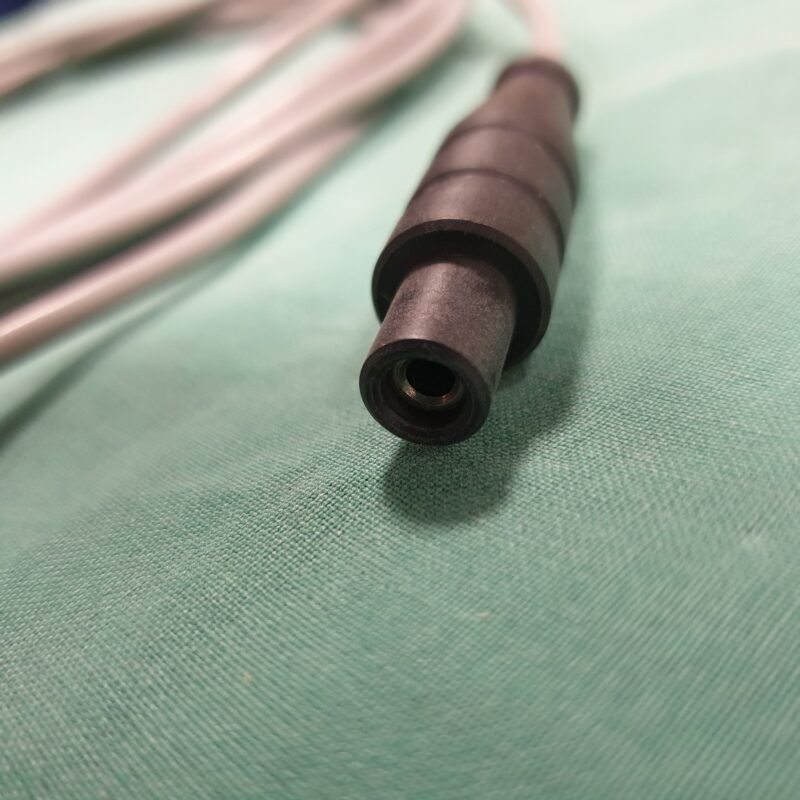

Zustand: Ungeprüft

• Dieses HF Kabel wurde nicht vollständig getestet und könnte daher Funktionsfehler aufweisen.

• Die Bilder sind Teil der Beschreibung – Sie erhalten genau das, was abgebildet ist.

• Der angegebene Preis bezieht sich auf einen einzelnen Fußschalter.

Hinweis: Aufgrund gesetzlicher Bestimmungen werden alle Geräte als defekt für Bastler oder Ersatzteilspender verkauft, auch wenn sie funktionsfähig sind. Der Käufer wird ausdrücklich darauf hingewiesen, dass er bei der Inbetriebnahme die Vorschriften des Medizinprodukte-Durchführungsgesetzes (MPDG) sowie der Medizinprodukte-Betreiberverordnung (MPBetreibV) einzuhalten hat. Eine sicherheitstechnische Kontrolle des Geräts muss wie vorgeschrieben durchgeführt werden. Für die Einhaltung ist der Käufer selbst verantwortlich.